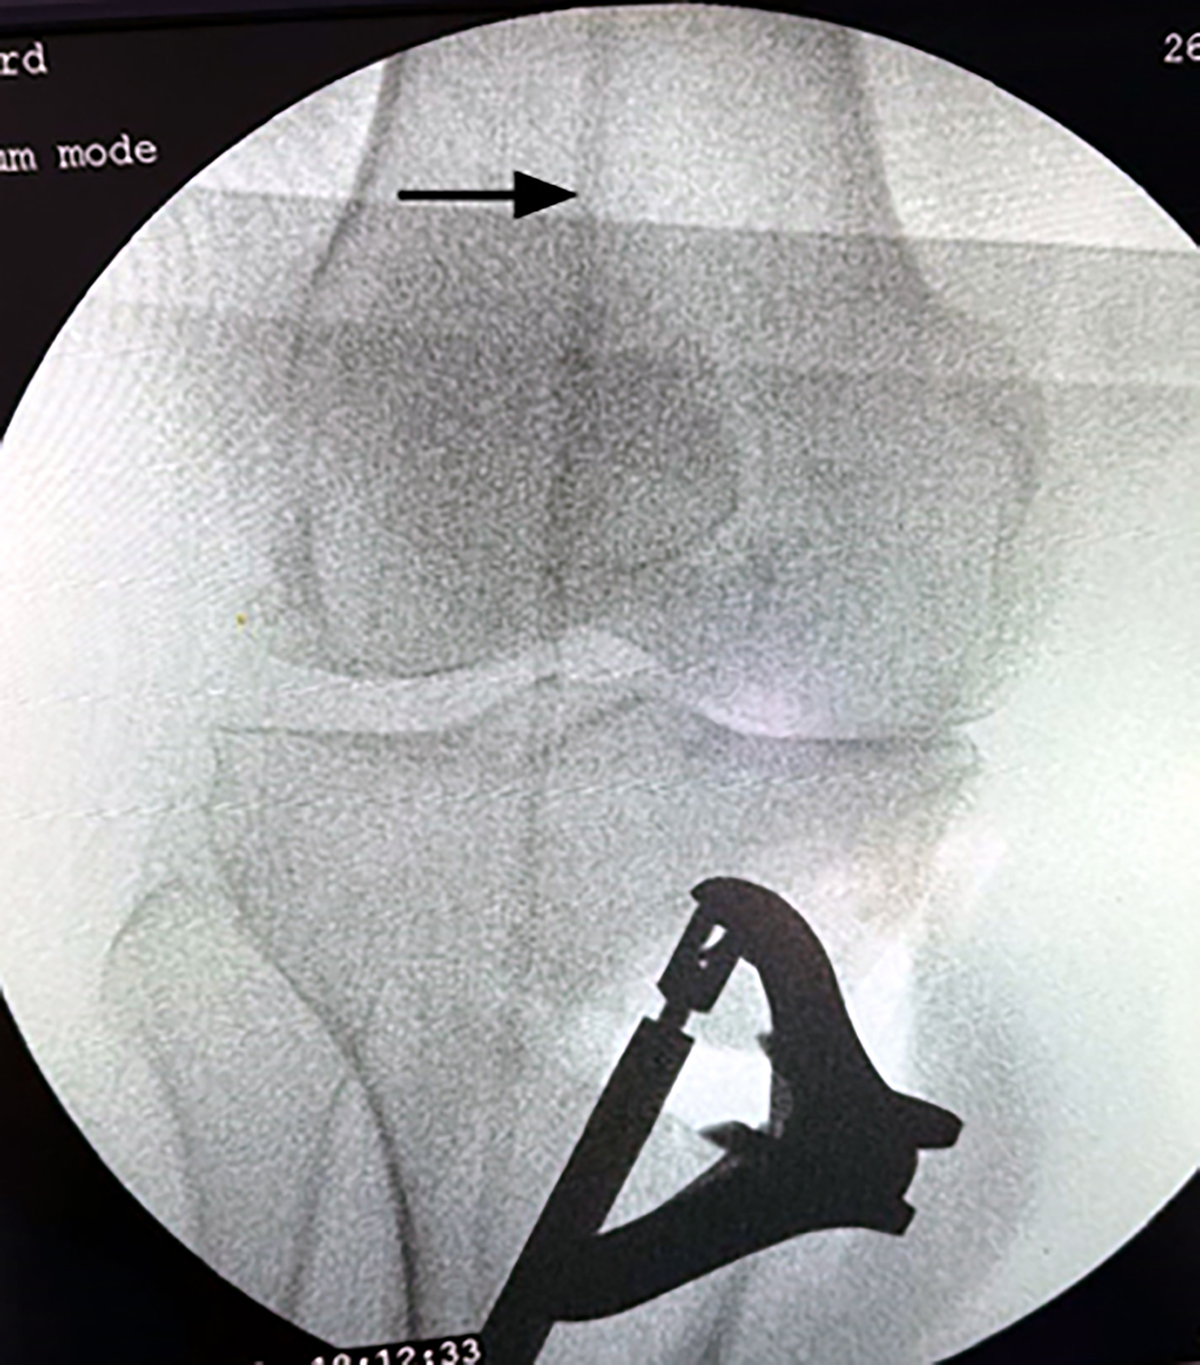

Figure 3

After opening the wedge, the alignment obtained was checked under fluoroscopy by a metallic wire (Black arrow).